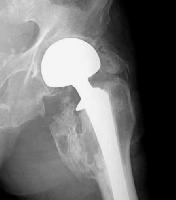

picture of Heterotopic bone formation in hip , another picture here

picture of radiation port after total hip

External beam radiation External beam radiation has also demonstrated efficacy in prevention of HO after total hip arthroplasty. A year 2004 meta-analysis of seven randomized studies that compared radiation to NSAIDs concluded that radiotherapy is more effective, but the absolute difference in the rates of clinically significant HO are quite small, on the order of one percent. A single dose regimen of 700 or 800 centigray is recommended. Radiation may be administered preoperatively (within 24 hours) or postoperatively (within 72 hours). If cementless prosthetic components are used, the ingrowth areas should be shielded from the radiation beam. Currently, there is no clinical evidence supporting malignant transformation following this type of single dose regimen.